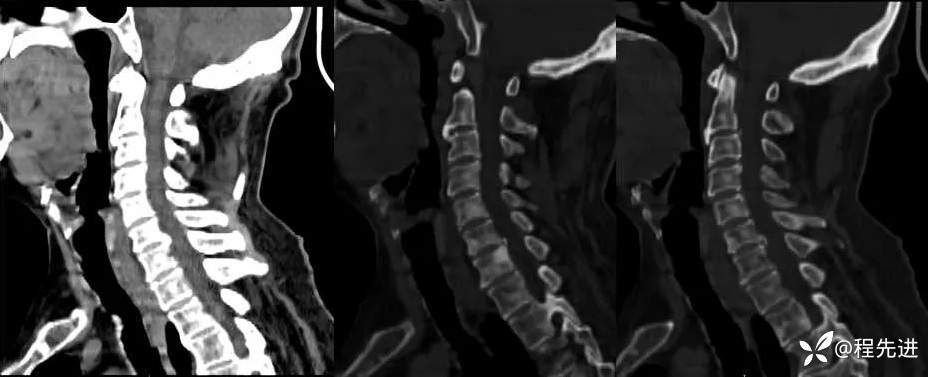

颈椎: